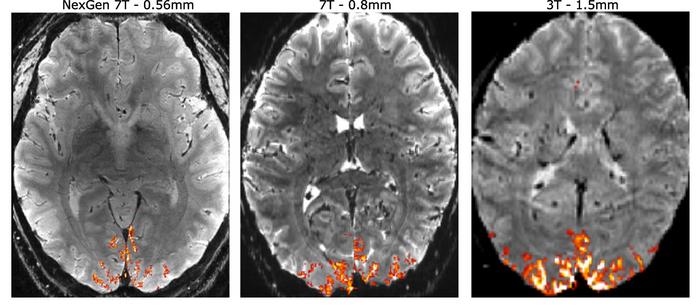

An intense international effort to improve the resolution of magnetic resonance imaging (MRI) for studying the human brain has culminated in an ultra-high resolution 7 Tesla scanner that records up to 10 times more detail than current 7T scanners and over 50 times more detail than current 3T scanners, the mainstay of most hospitals.

The dramatically improved resolution means that scientists can see functional MRI (fMRI) features 0.4 millimeters across, compared to the 2 or 3 millimeters typical of today's standard 3T fMRIs.

To take advantage of the new hardware technology, Suhyung Park, Rüdiger Stirnberg, Renzo Huber, Xiaozhi Cao and Feinberg designed new pulse sequences of precisely timed gradient pulses to rapidly achieve ultra high resolution. The smaller voxels, measured in units of cubic millimeters and less than 0.1 microliter, provide a 3D image resolution that is 10 times higher than that of previous 7T fMRIs and 125 times higher than the typical hospital 3T MRI scanners used for medical diagnosis.

“A 3T fMRI scanner can resolve spatial details with a resolution of about 2 to 3 mm. The cortical circuits that underpin thought and behavior are about 0.5 mm across, so standard research scanners cannot resolve these important structures,” Gallant said.

But again, the 3 mm resolution of a 3T fMRI can distinguish only large veins, not the small ones that could indicate activity within microcircuits.

The NexGen 7T will allow neuroscientists to pinpoint activity within the thin cortical layers in the gray matter, as well as within the narrow column circuits that are organized perpendicular to the layers. These columns are of special interest to Gallant, who studies how the world we see is represented in the visual cortex. He has actually been able to reconstruct what a person is seeing based solely on recordings from the brain's visual cortex.

"The machine that David has built, in theory, should get down to 500 microns, or something like that, which is way better than anything else — we're very near the scale you would want if you're getting signals from a single column, for example," Gallant said. "It's fantastic. The whole thing about MRI is how big is the little volumetric unit, the voxel, the three-dimensional pixel that you're recording from. That's the only thing that matters."